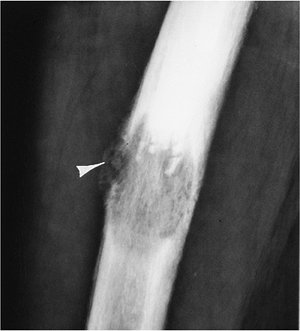

FIGURE 10-2

Moth-eaten. Lateral view of the femur showing a destructive lesion with poorly defined margins and a pathologic fracture anteriorly (arrowhead) as the result of metastasis. |